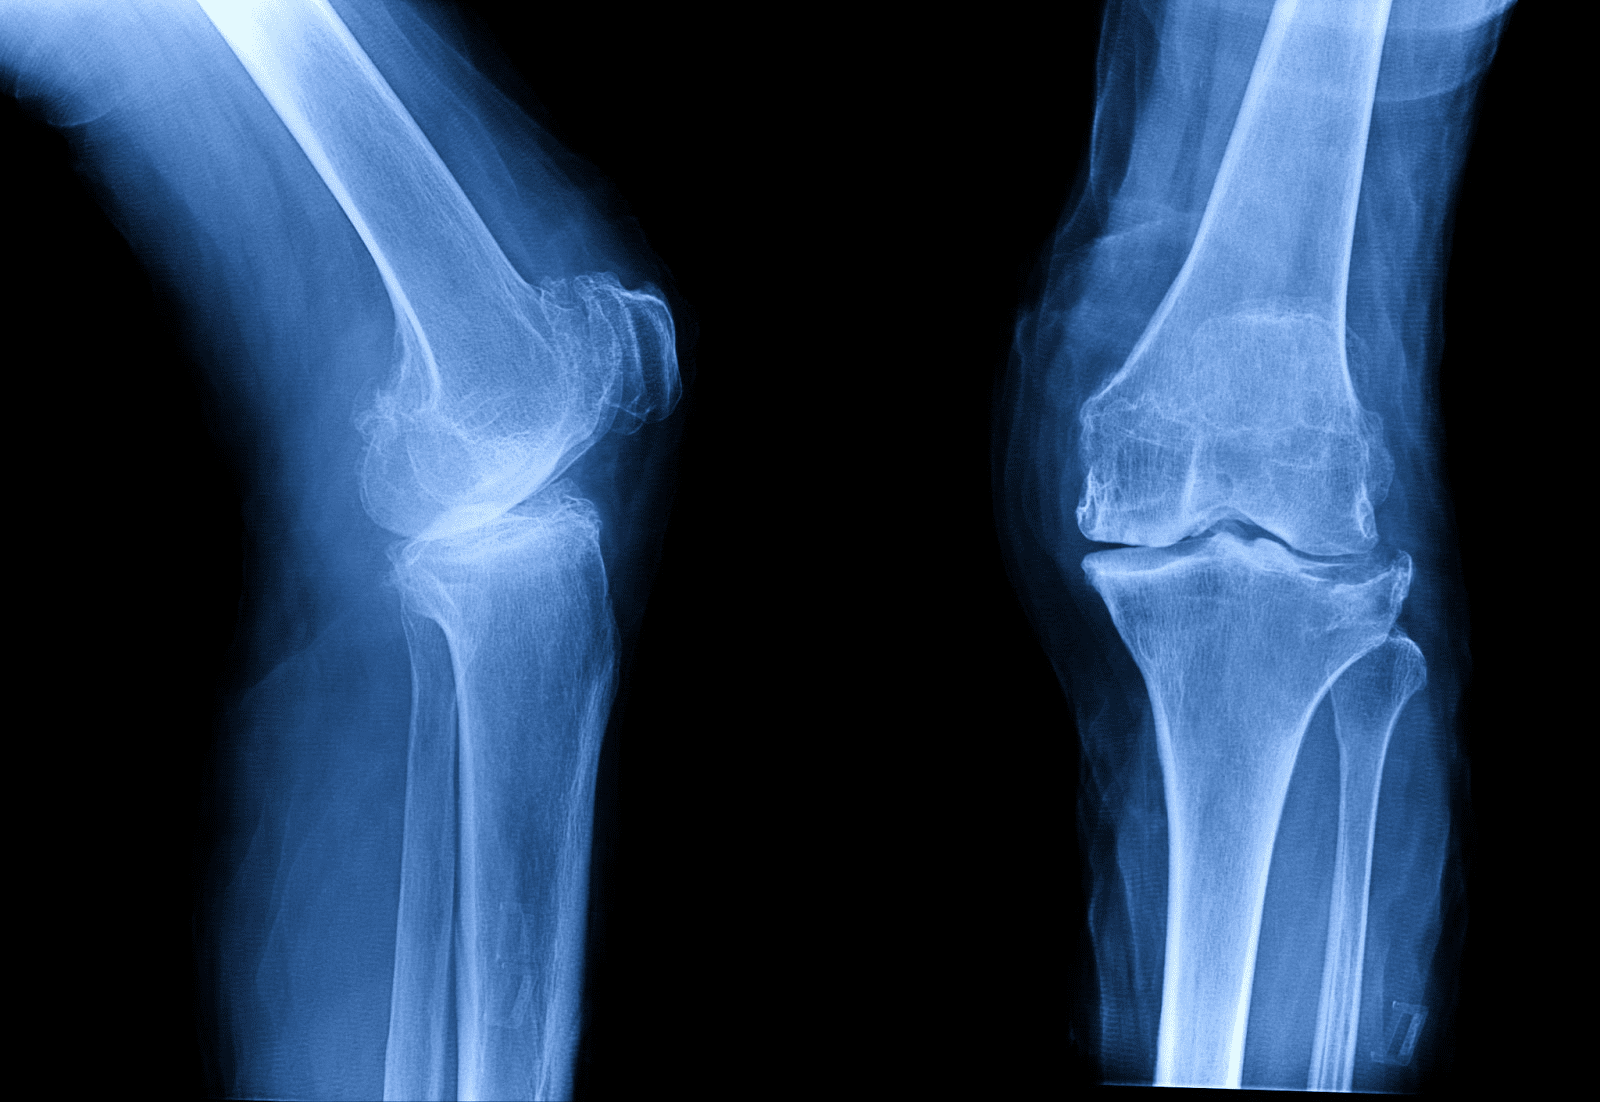

中國科學家團隊近日公佈一項突破性的醫療發明,名為Bone-02的骨骼膠水,能夠在短短三分鐘內修復骨折,有望徹底改變骨科手術的未來。這項研究由浙江省邵逸夫醫院(Sir Run Run Shaw Hospital)的林賢豐博士(Dr. Lin Xianfeng)領導,其靈感來自於牡蠣在潮濕且動態的表面上依然能牢固附著的非凡能力。與傳統的金屬植入物不同,Bone-02具有生物可吸收性,會隨著骨骼的自然癒合過程逐漸溶解,從而免除了患者需要接受第二次手術以移除固定物的痛苦與風險。目前,該黏合劑已在超過150名患者身上成功進行試驗,即使在血液豐富的複雜環境中,也展現出令人印象深刻的強度、安全性與快速黏合效果。

Bone-02的研發根植於仿生學,模仿了牡蠣如何抵禦海浪與水流,緊密附著於水下物體表面的原理。這種黏合劑複製了牡蠣的天然韌性,為外科醫生提供了一種強大的工具,特別適用於傳統黏合劑經常失效的富血環境。在塗抹後的兩到三分鐘內,Bone-02便能以超過400磅的卓越黏合力固定斷裂的骨骼。其快速作用的特性與持久的耐用性,不僅大幅提升了手術效率,也為患者帶來了更為順暢的康復過程。未來,其應用範圍更可能擴展至牙科手術、關節修復,甚至是在分秒必爭的戰地醫療中發揮關鍵作用。

Bone-02的臨床試驗已涵蓋超過150名患者,並取得了令人鼓舞的成果。參與試驗的醫生報告指出,以往需要使用鋼板和螺釘的複雜手術,現在僅需過去一小部分的時間即可完成。除了速度上的優勢,該黏合劑還表現出強大的物理性能,其剪切強度達到0.5兆帕(MPa),抗壓強度約為10兆帕,足以媲美標準的金屬植入物。更重要的是,人體對Bone-02的耐受性良好,未出現重大的安全疑慮。這些發現表明,它有潛力在全球醫院中取代許多傳統的骨折固定方法,並對急診醫學產生深遠影響。